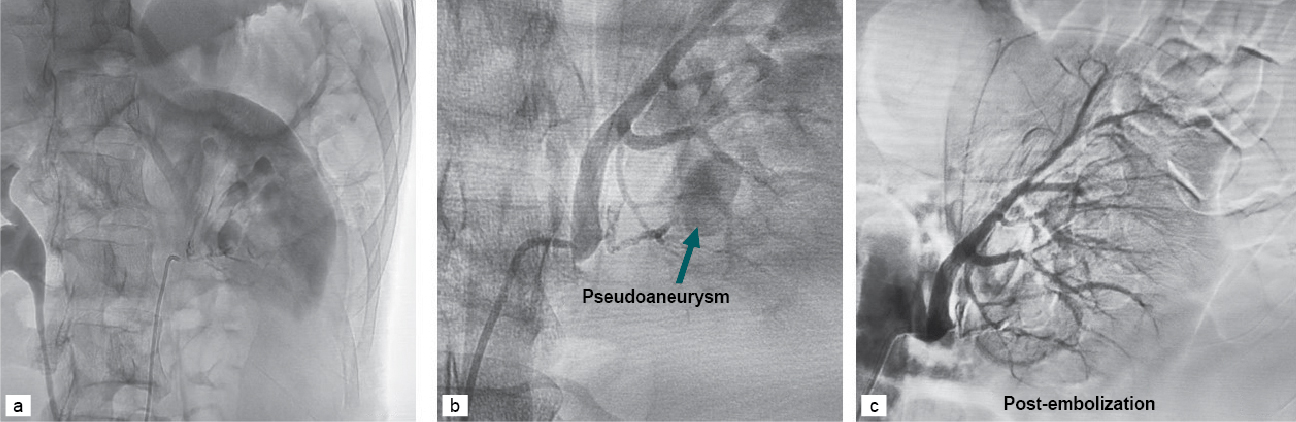

The embolization procedure was performed under local anesthesia. Retrograde Seldinger technique was utilized through the opposite femoral arterial access. A diagnostic renal angiogram was performed using a Cobra catheter. Once the pseudoaneurysm was confirmed, the 5 Fr Cobra catheter and Progreat catheter were used to perform super-selective catheterization and embolization using 50% N-butyl-2-cyanoacrylate (NBCA) + Lipiodol (Fig. 2). Check angiogram of the renal artery showed complete embolization of the pseudoaneurysm with normal opacification of the rest of the renal arterial branches.

Figure 2. (a and b) Diagnostic renal angiogram showing a pseudoaneurysm involving the lower pole. (c) Post-embolization renal angiogram.